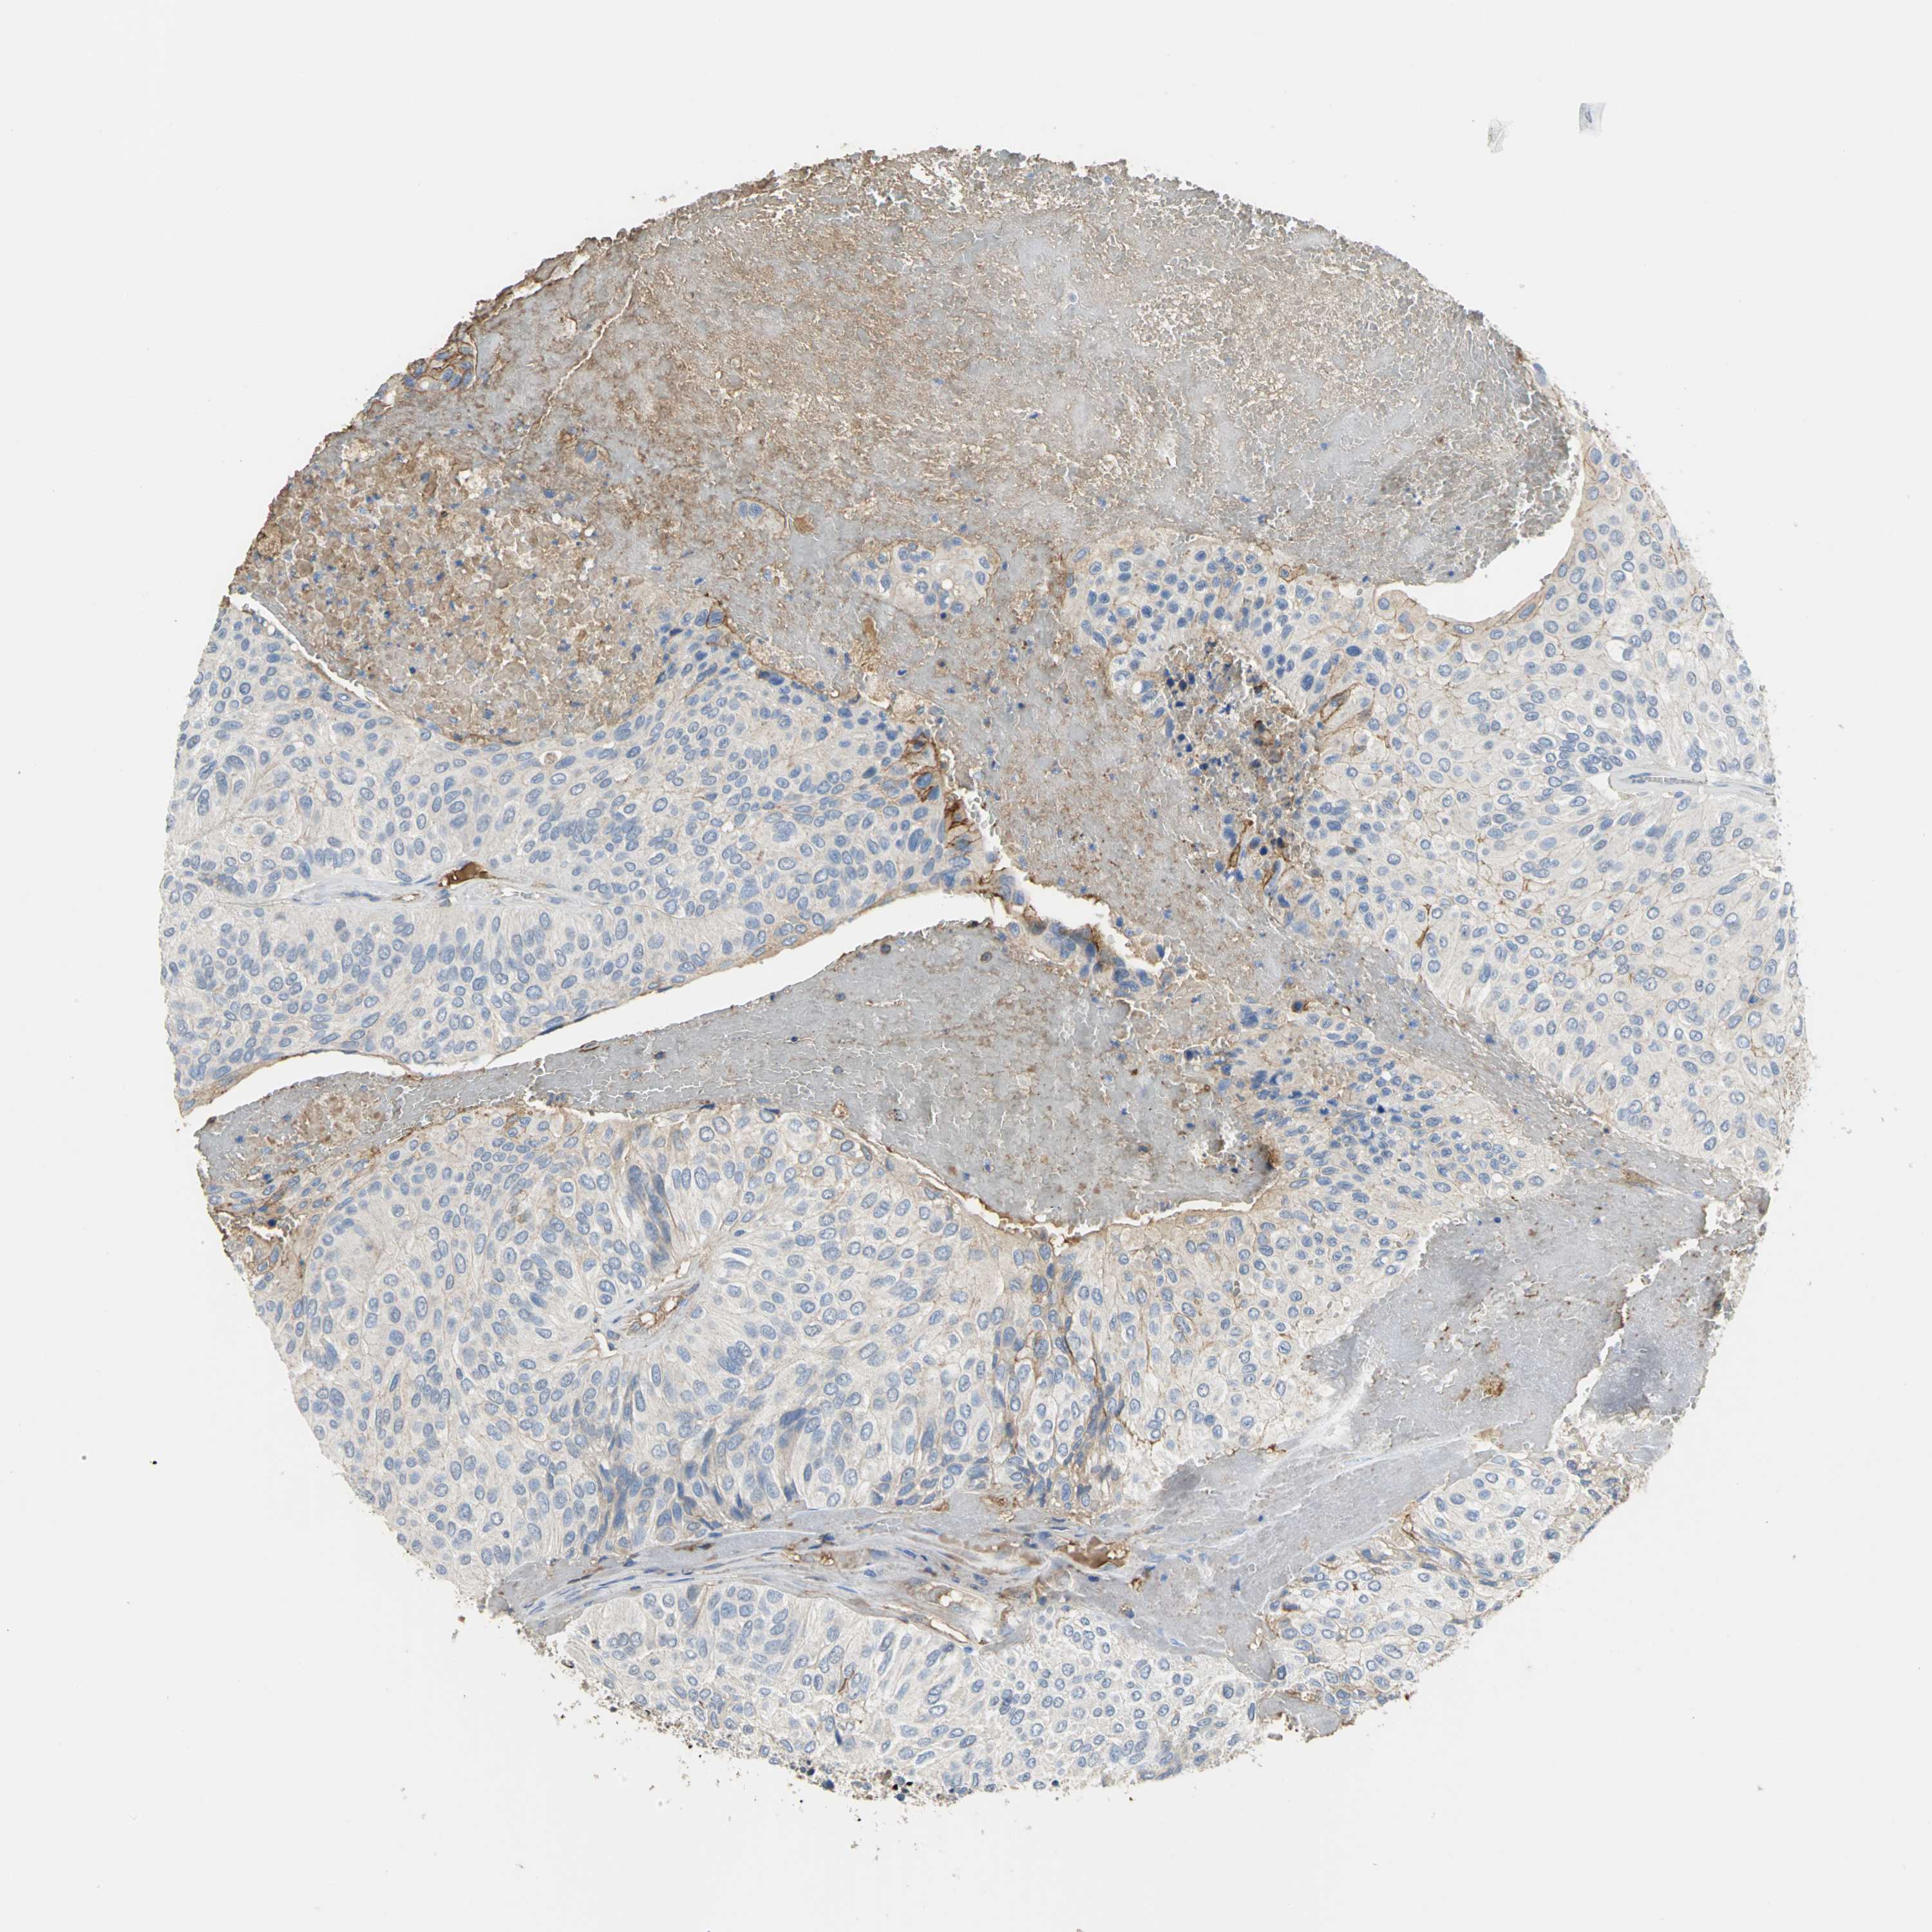

UROTHELIAL CANCER - Protein expressioni

A mouse-over function shows sample information and annotation data. Click on an image to view it in a full screen mode. Samples can be filtered based on level of antibody staining by selecting one or several of the following categories: high, medium, low and not detected. The assay and annotation is described here.

Note that samples used for immunohistochemistry by the Human Protein Atlas do not correspond to samples in the TCGA dataset.

Antibody stainingi

Antibody staining in the annotated cell types in the current human tissue is reported as not detected, low, medium, or high, based on conventional immunohistochemistry profiling in selected tissues. This score is based on the combination of the staining intensity and fraction of stained cells.

Each image is clickable and will lead to virtual microscopy that enables deeper exploration of all samples and also displays staining intensity scores, fraction scores and subcellular localization as well as patient and tissue information for each sample.

Antibody HPA005495

Antibody HPA064686

Staining

High

Medium

Low

Not detected

Intensity

Strong

Moderate

Weak

Negative

Quantity

>75%

75%-25%

<25%

None

Location

Nuclear

Cytoplasmic/membranous

Cytoplasmic/membranous,nuclear

Urothelial carcinoma, High grade

Urothelial carcinoma, Low grade

Urothelial carcinoma, NOS